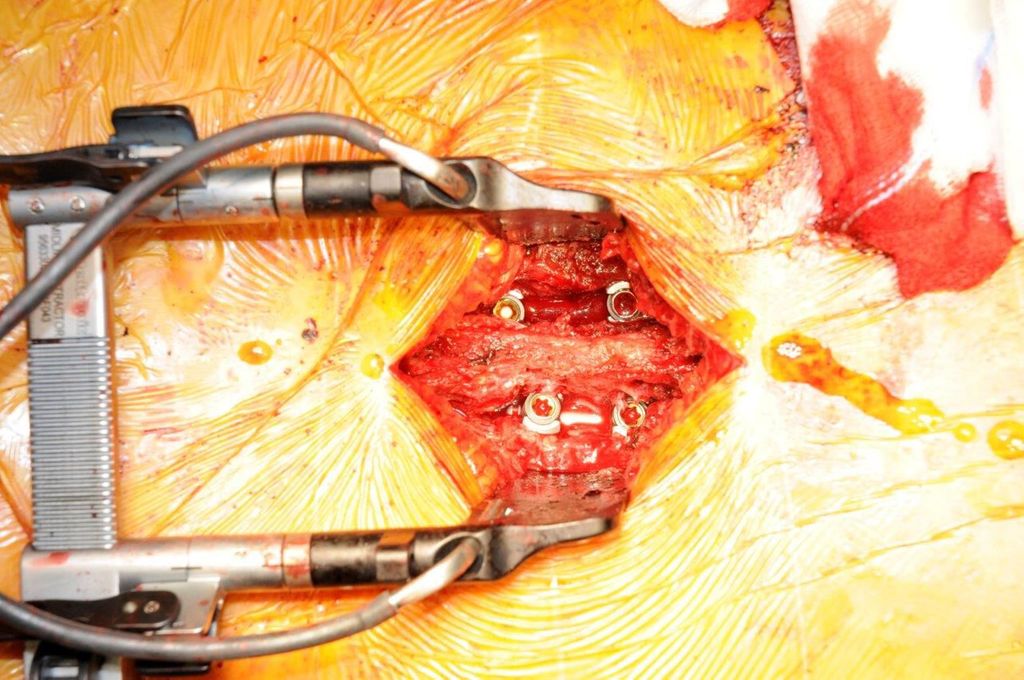

Beispiel für die Implantation zervikaler Pedikelschrauben. In diesem Fall kam es bei einem 61-jährigen Patienten 10 Jahre nach anteriorer zervikaler Diskektomie und Fusion (ACDF) C4/5 und ventraler Verplattung C4–6 zu einer Ankylosierung auch von C6/7. Nach Sturz kam es zu einer Fraktur bei C6/7 mit begleitender Bogenfraktur und auch Beteiligung der dorsalen Ligamenta (Abb. 1 und 2). Klinisch bestanden ausgeprägte Nackenschmerzen und kein neurologisches Defizit. Es wurde die Indikation der dorsalen Verschraubung von C4 auf Th1 gestellt. Intraoperativ wurde routinemäßig zusätzlich eine kleine Referenzschraube in einer Lamina – entfernt von der Dornfortsatz-Referenzklemme für die Navigation – gesetzt. Mit dieser konnte intraoperativ die Genauigkeit der Navigation exakt überprüft werden (Abb. 4 und 5). Mittels navigierter High-Speed-Fräse wurden die Schraubenkanäle vorgebohrt (Abb. 6), im Anschluss wurde der Bohrkanal ausgetastet und die Schrauben wurden implantiert. Abbildung 7 zeigt eine Röntgenkontrolle 3 Monate postoperativ.